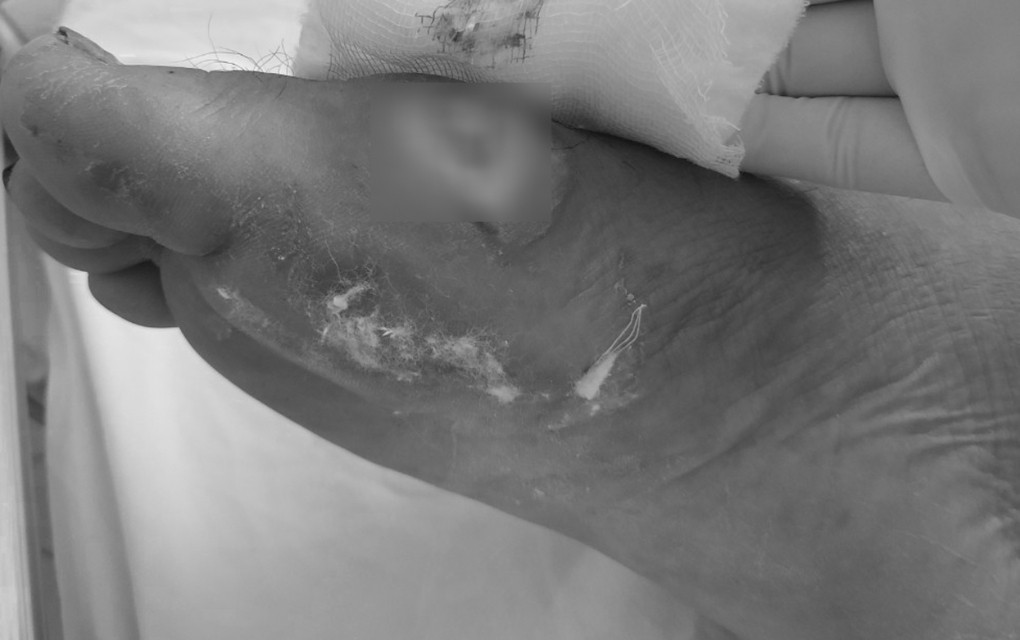

Theo bác sĩ Hàm, biểu hiện bệnh Whitmore rất đa dạng và phức tạp. Bệnh nhân có thể sốt cơn hoặc sốt kèm theo lạnh run, sốt kéo dài. Cùng với đó là suy hô hấp, loét da, viêm đường tiết niệu, viêm phổi, áp xe phổi, áp xe ở gan, lách, nhiễm trùng huyết, suy đa phủ tạng... Bệnh thường chẩn đoán nhầm với viêm phổi, lao phổi, áp xe cơ, bệnh nhiễm trùng huyết do các vi khuẩn khác.

Hiện nay, chưa có vaccine phòng bệnh Whitmore, do đó bác sĩ Hàm khuyến cáo người dân hạn chế tiếp xúc với tác nhân gây bệnh, bao gồm đất, nước, bùn lầy, đặc biệt là những nơi có ô nhiễm nặng. Người có vết thương hở trên da, vết loét hoặc bỏng và người thường xuyên làm việc ngoài trời, phải tiếp xúc trực tiếp với đất và nước nhiễm bẩn cần trang bị đầy đủ giày, dép và găng tay cao su. Đồng thời, cần đảm bảo vệ sinh sạch sẽ trước và ngay sau khi tiếp xúc.